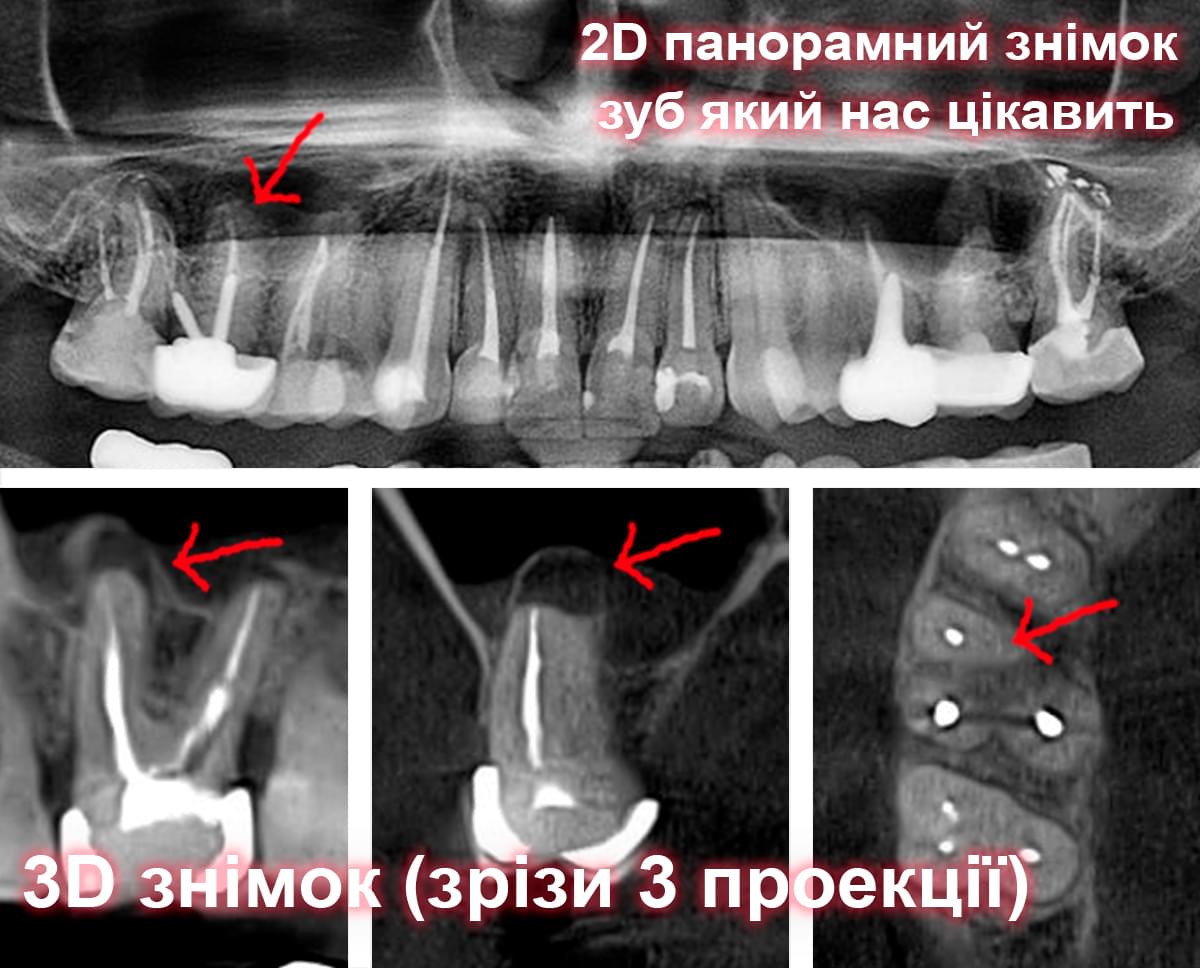

Візуальне порівняння (Кейс одного пацієнта)

Зуб — це не просто монолітний об'єкт, а складна система мікроканалів. На плоскому 2D-знімку вони часто перекривають один одного, створюючи ілюзію простої анатомії.

Непомічений канал — це джерело майбутньої інфекції та причина «загадкового» болю після лікування. Завдяки високій роздільній здатності обладнання MyRay, лікар бачить кожен мікронний канал ще до того, як візьме до рук інструмент.

Коли коріння «ховає сюрпризи» - Корені зубів часто мають складну кривизну, гачкоподібні закручення або розгалуження, які на звичайному 2D-знімку накладаються один на одного, створюючи ілюзію прямого каналу. На плоскій картинці неможливо побачити реальний об'єм та напрямок вигину, що критично важливо при видаленні «зубів мудрості» або ендодонтичному лікуванні. КТ MyRay дає змогу лікарю заздалегідь побачити 3D-геометрію кожного кореня, оцінити його близькість до нижньощелепного нерва чи гайморової пазухи та підібрати правильну тактику роботи. Це мінімізує ризики поломки інструменту в каналі або травмування сусідніх структур, перетворюючи складну хірургію на прогнозовану процедуру.